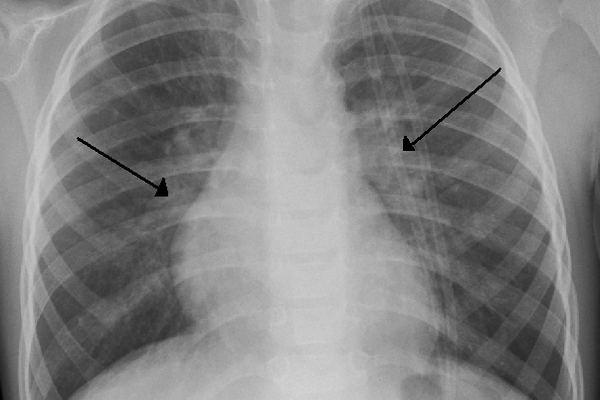

Radiografía de un niño con bronquiolitis por VRS que muestra la típica plenitud perihiliar bilateral.